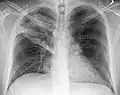

The discovery of x-rays made it possible to determine the anatomic type of pneumonia without direct examination of the lungs at autopsy and led to the development of a radiological classification. Early investigators distinguished between typical lobar pneumonia and atypical (e.g. Chlamydophila) or viral pneumonia using the location, distribution, and appearance of the opacities they saw on chest x-rays. Certain x-ray findings can be used to help predict the course of illness, although it is not possible to clearly determine the microbiologic cause of a pneumonia with x-rays alone.

-

Normal AP CXR

Normal lateral CXR -